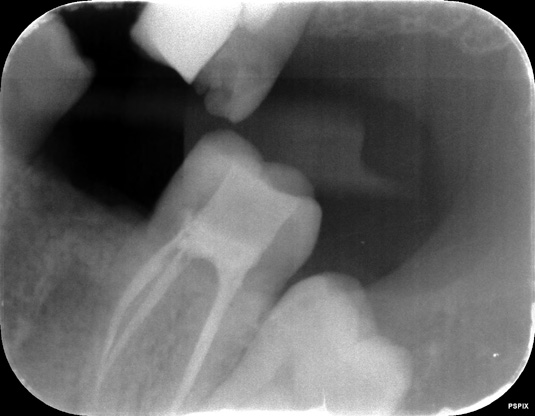

De bovenste foto is genomen op 24-2-2021

door tandarts Baeten

De weledelgeleerde tandarts Andre Padrao ziet hier twee wortelpunt ontstekingen , en een groot gat tot aan de furca . Een andere foto had hij niet tot bechikking

Over deze rongenfoto is element 35 bijna zwart (niet te zien) 14.42